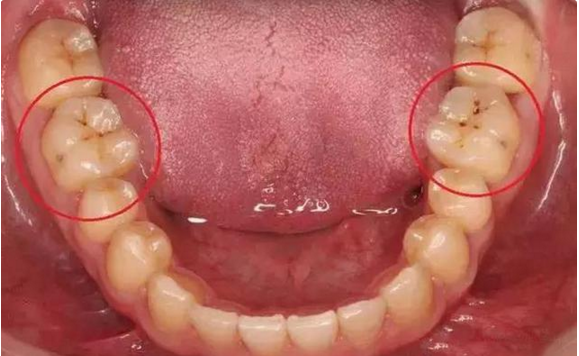

02另一種則是牙齒出現了或深或淺的齲壞,從外面看就表現為一個黑點,通常位於窩溝點隙(牙面上點狀或線狀凹陷)。齲齒的罪魁禍首是口腔中的某些細菌,但它們破壞牙齒也是需要時間的,從初期的變色到最終形成齲洞,通常需要1年半到兩年。在此期間,我們多留心自己的牙齒,完全可能把齲壞扼殺在萌芽階段。如何才能及時發現這種隱匿的蛀牙呢?找位好牙醫,半年檢查牙齒!

一旦確認牙齒上的小黑點是齲齒就應該儘早修補,以阻止病變的發展。如果任由其繼續發展就會變成明顯的齲洞,這時患者會對冷熱酸甜等食物刺激敏感;當損傷進一步到達牙髓(即老百姓說的「牙神經」),就會疼痛難忍,嚴重影響日常生活。臨床上見到很多人都會等到牙痛得受不了,才到醫院就診。這時通常不能靠單純補牙來解決問題,可能還要做根管治療甚至拔除患牙、進行假牙修復,費時費力又費錢,人還遭罪,可謂「小洞不補,大洞吃苦」。

因此,平時應注意自檢,觀察牙齒顏色、形狀、質地的變化,還要每半年進行全面的口腔檢查,如果有齲齒,就應該早發現早治療。